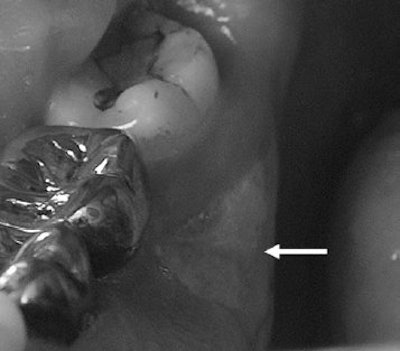

| A 61-year-old man with metastatic prostate cancer treated with zoledronate presents with painful bone exposure of the right mandible (arrow). Phal PM, Myall RWT, Assael LA, Weissman JL, "Imaging Findings of Bisphosphonate-Associated Osteonecrosis of the Jaws," American Journal of Neuroradiology, Vol. 28:6, pp 1139-1145. © American Society of Neuroradiology. |

In this retrospective study, Dr. Phal's group included 15 patients on bisphosphonates who developed osteonecrosis of the jaws. Among the 11 female subjects, six had breast cancer, three had osteoporosis, and two had multiple myeloma. Among the four male patients, there were two cases of prostate cancer, one of multiple myeloma, and one of osteoporosis.